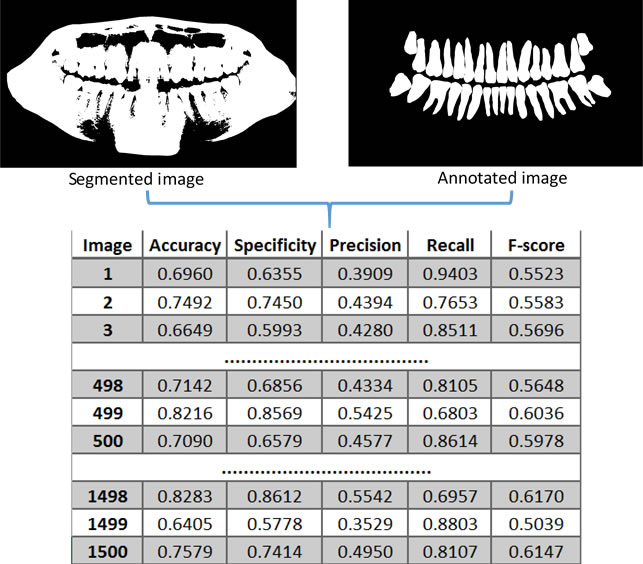

4.2 Performance analysis of the segmentation methods

The following metrics were used to evaluate the segmentation methods studied: Accuracy, specificity, precision, recall (sensitivity) and F-score, which are commonly used in the field of computer vision for performance analysis of segmentation. Table 7 presents a summary of these metrics.

Only the image ROIs were considered to calculate the metrics for the evaluation of the segmentation methods. The process presented in Figure 6 was carried out on all the segmented images obtained by each one of the 10 segmentation methods analyzed. Figure 7 illustrates the steps of the performance evaluation over 10 segmentation methods (see also Table 9 for a list of the evaluated methods).

4.2.2 Computing the metrics over the data set

Table 8 summarizes the process to calculate the accuracy for all images in each category, using only one segmentation method. Parameters of each method were optimized for best performance. On each category, the average accuracy was computed. After that, to find the accuracy for all images in the data set, the average accuracy was multiplied by the number of images in each category, obtaining a weighted sum for all images in the data set ( images). By dividing by the number of images in the whole data set, we were able to find the average accuracy of the data set for one segmentation method. The same process was performed to calculate all other metrics (specificity, recall, precision and f-score), over each segmentation method. The segmentation methods evaluated in this work are summarized in Table 9. Next, each one of the methods are discussed and evaluated.

Tables 10 and 11 present samples of the results obtained by each of the segmentation methods evaluated, in each category. Table 12 summarizes the overall averages obtained by calculating the metrics, which were applied to evaluate the performance of each segmentation method. From Table 12, we can observe that the splitting and merging-based and the sobel methods achieved almost perfect results in the specificity (which corresponds to the true negatives). This could be explained due to the characteristics of the two methods to focus on the edges. Similarly, the fuzzy C-means and canny methods also had over 90% with respect to specificity. In contrast, these four segmentation methods obtained poor results in relation to the recall metric (which privileges the true positives in the evaluation). Thus, the images, segmented by algorithms based on splitting and merging, fuzzy C-means, canny and sobel, showed a predominance of true negatives in their results. However, when segmentation results in a predominance of elements of a class (for example, true negatives), it indicates that for a binary classification problem, the result of the segmentation algorithm is equivalent to the random suggestion of a class. Therefore, algorithms based on splitting and merging, fuzzy C-means, canny and sobel presented poor results when applied to the data set images used in the present work.

The results presented in Table 12 also show that the niblack reached the highest value of the recall metric (approximately 83%), indicating that the images segmented by niblack presented the highest number of true positives (pixels corresponding to the objects of interest in the analyzed images) and, therefore, few false negatives with respect to the other methods of segmentation evaluated. Niblack also obtained approximately 82% in relation to the specificity metric, which corresponds to the true negatives that were correctly identified. Besides niblack, only the marker-controlled watershed method reached above 80% of the recall metric. The marker-controlled watershed obtained lower results than the Nibliack method in all other analyzed metrics. The active contour without edges and the level set segmentation methods obtained less than 70% of the recall metric; these methods also achieved poorer results when compared to the Niblack and marker-controlled watershed methods.

Considering the results, one can state that the segmentation process of panoramic X-ray images of the teeth based on thresholding, achieved a significant performance improvement when a local threshold (niblack method) was used, instead of using a single global threshold (basic global thresholding). Niblack was the one which presented superior performance to segment teeth.